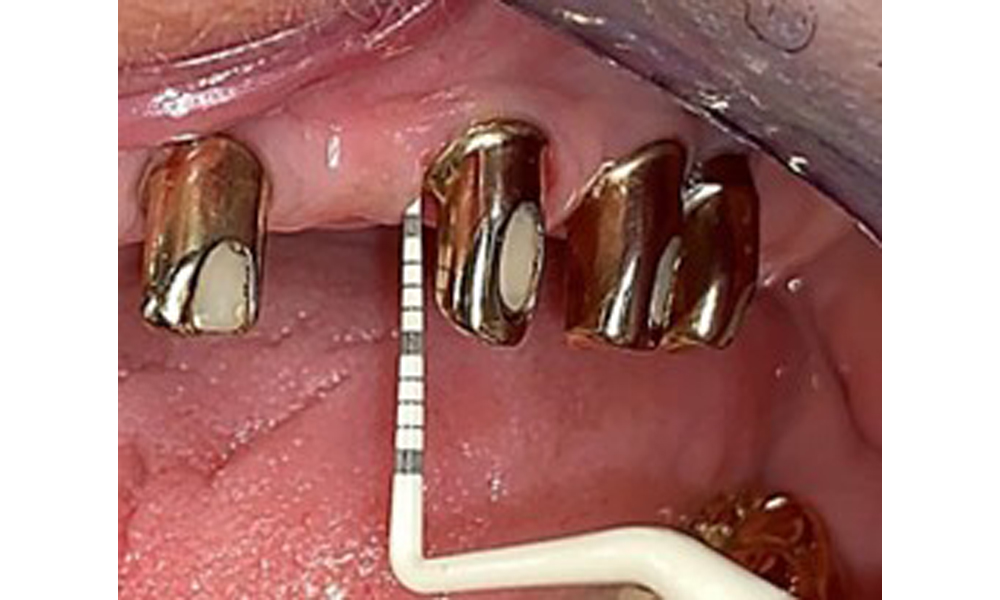

Денталните открития са следните: Комбинирани снемаеми протези на импланти и телескопични протези, поддържани от зъби, на импланти 15, 13, 21, 23, 24, 25 и зъб 11 (фиг. 1, фиг. 2, фиг. 3). Пациентът е снабден с фиксирана долночелюстна протеза. Над зъби 37-34 и 45-47 бяха налични адекватни мостове (фиг. 4), краищата на коронките бяха интактни и нямаше активен кариес. Върху зъб 43 имаше композитна пломба с маргинална празнина. Имаше рецесия на долната гингива, която разкриваше от 1 до 3 mm от кореновата повърхност. Това се отнася и за 11.

Оклузален изглед: Горна челюст със зъб и телескопични протези, поддържани от импланти

Фиг. 2: Оклузален изглед: Горна челюст със зъб и телескопични протези, поддържани от импланти